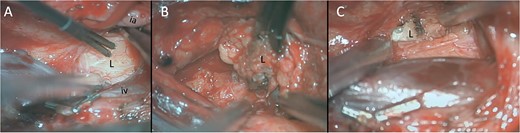

Intra-operative pictures. Direct electrical stimulation of lesion (L) when first reached (A) located between and posterior to the iliac artery (ia) and iliac vein (iv). Lesion contained both fatty (B) and pearly appearing flakes (C).

We began the resection of the mass with an operative microscope. Ultrasound was utilised to aid in the localisation of the lesion and guide resection in both cranial and caudal directions to find the poles of the lesion. Throughout this process, neuromonitoring remained quiet and stimulation did identify motor nerves. The lesion was internally debunked to aid in resection and was found to contain a gray ‘snowflake’-like material, then dissected out and removed (for intra-operative imaging, see Fig. 2). Intra-operative frozen section consultation revealed an epithelial-lined cyst.